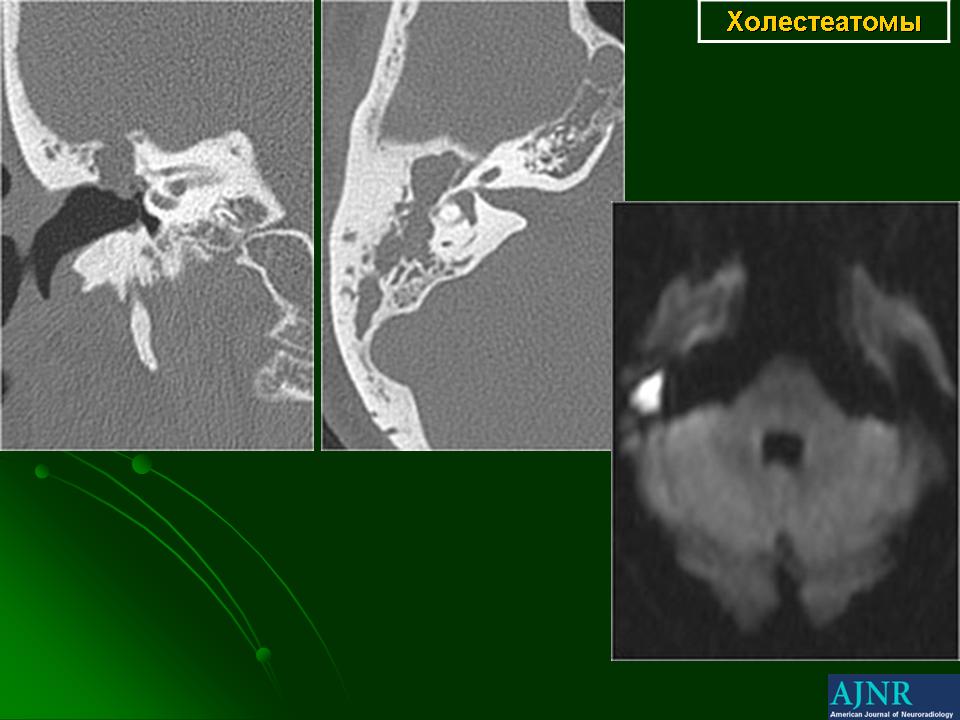

Диагностика холестеатомы представляет определенные трудности. Основными методами выявления холестеатомы последние несколько десятилетий остаются отоскопия (отомикроскопия) и рентгенологические методы (рентгенография в различных укладках и компьютерная томография). Компьютерная томография височных костей позволяет диагностировать холестеатому намного чаще, чем обычная рентгенография, однако степень достоверности данной диагностики остается невысокой, так как плотность холестеатомы практически соответствует плотности грануляционной ткани. Поэтому чувствительность метода КТ в диагностике холестеатомы составляет всего 71% при специфичности 55% [50]. Кроме того, следует учитывать, что указанный метод требует не только дорогостоящего оборудования, но и высококвалифицированных рентгенологов со специальной подготовкой, позволяющей им правильно интерпретировать полученные результаты.

ID: 10742 Cholesteatoma Dr Erik Ranschaert - 15 Sep 2010 Diffusion MRI (non-EPI DWI or TSE DWI) allows to identify with high accu...